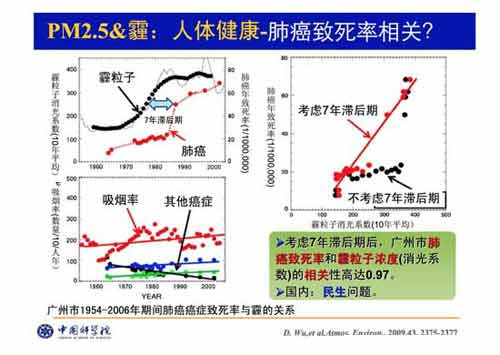

前段时间,一条“雾霾与肺癌有着“七年之约”,即出现雾霾严重的年份後,相隔七年就会出现肺癌高发期。”的博客一出,立刻在网上引起高度关注。关於雾霾与肺癌的“七年之约”成为人们关注的焦点。

“七年之约” 尚无定论

虽然已经证实了PM2.5会提高患肺癌的风险率,但关於相隔七年就会出现肺癌高发期的言论,目前还没有相关研究能够证实。

“雾霾与肺癌的7年之约”的说法最早出现在一家媒体对广州市肺癌患者发病率上升的报导中,该报导援引自广东省气象局首席气象专家吴兑2009年对广州市肺癌发病率上升的研究结果:考虑7年滞後期後,广州市肺癌致死率和霾粒子浓度的相关性高达0.97,这意味着今天呼吸到的“有毒”空气,或许在7年之後才会产生“致命危害”。经过七八年以後,肺癌死亡率随之提高,这二者之间的时间滞後关系比较吻合。

但在这篇报导中,这位专家还有一句补充说明被网友所遗漏:“但肺癌的致病机理与其确切的死亡率提高的真正原因,我们仍然希望由呼吸病与流行病学专家来共同完成研究。”

众多专家均表示,“灰霾与肺癌‘七年之约’的说法有些夸张丶不准确,截至目前流行病学调查对此没有大量深入的直接研究。”